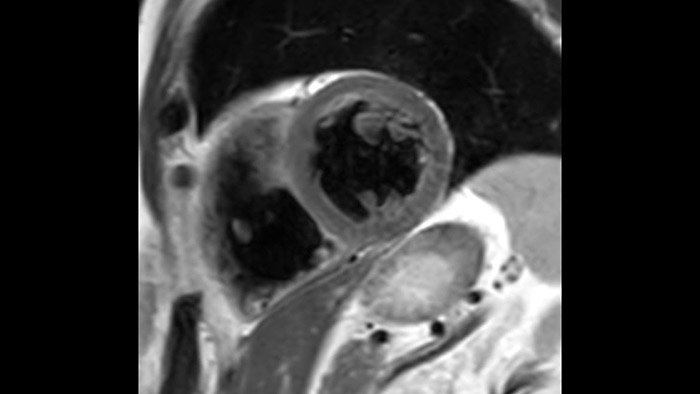

Combinando la smart-sync2 sviluppata dalla NORTHH MEDICAL (un sistema di Doppler a ultrasuoni compatibile con la MRI) con un sistema di RM Philips, abbiamo reso possibile la RM fetale cardiaca per fornire informazioni diagnostiche aggiuntive che possono aiutare nella diagnosi delle patologie cardiache congenite fetali, nel caso in cui l’ecocardiografia non sia sufficiente. Per saperne di più sullo smart-sync e scoprire cosa ne pensano i nostri clienti, clicca qui.